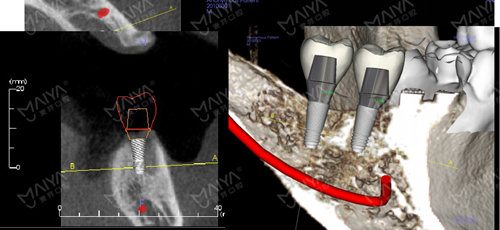

完成的影像数据、及三维数据模型,经数据云传输至MAC数字化精确方案设计中心,通过AI人工智能软件、循证医学病例数据库,融入咬合关系、基台牙冠等修复信息,完成咬合关系重建、模拟种牙理想路径,实现“以修复为导向”的种植方案设计。

种植牙修复,除了功能还兼顾美学,基于以修复为导向的核心理念,麦芽口腔MAC种牙方案设计,不仅能找到理想的植入路径,还能针对独立个体,设计符合红白美学、颜面美学、生物力学、以及组织生物学的个性化基台与义齿修复冠,迷人笑容触手可得。

MAC数字化种牙方案数据集,借助云端传输,实现虚拟方案到临床现实的无缝转化,3D精确打印种牙导板,辅助医生完成理想路径植入,数字化精确切削完成基台与义齿修复体定制。